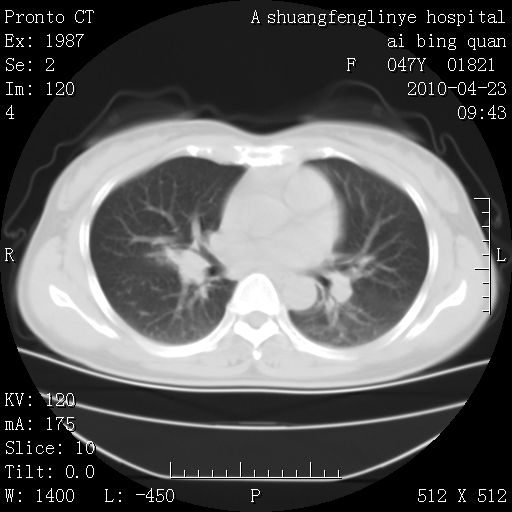

标题: CT25944:胸痛、气短、前几日高烧!肺Ca?请会诊! [打印本页]

标题: CT25944:胸痛、气短、前几日高烧!肺Ca?请会诊!

双肺多发结节,考虑转移瘤,肺癌肺转移不除外

周围型肺癌并肺转移

双肺多发结节,部分密度较高,最大结节边缘光滑。临床有“胸痛、气短、前几日高烧”病史。首选考虑:右肺感染性病变!建议积极消炎后复查!